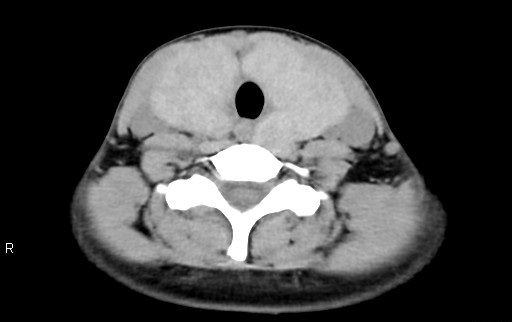

検査前は心拍数が120bpmを超えて、意思疎通困難・呼吸停止不可という患者の条件が非常に悪い中での撮影。最適心位相にて自動的に再構成された画像においてもブレが大きく、静止画像は全く期待できないと感じましたが、SnapShot Freeze2.0にて処理を行った画像はブレが大きく改善され大変きれいな画像であり、苦労することなく画像解析をすることが出来ました。

RevolusionCT_Sapporotokusyuukai_03.png